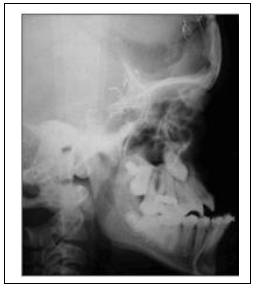

(Fonte: Lima DSC, Alonso N, Câmara PRP, Goldenberg C.; Rev. Bras. Otorrino, 3845 - Vol.)

Paciente sofreu acidente de trânsito e foi atendido no serviço de urgência e emergência apresentando fratura estendida bilateralmente nas suturas fronto-nasal, na parede medial e no assoalho das órbitas, alcançando as suturas fronto-zigomáticas e havendo completa separação do esqueleto facial da base do crânio. Clinicamente, apresentava afundamento do terço médio da face. Considerando a radiografia abaixo, a hipótese diagnóstica é